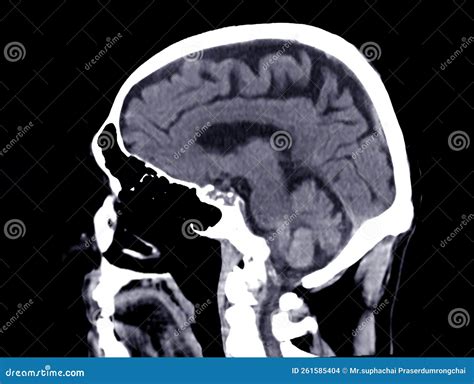

A brain cancer CT scan, or Computed Tomography scan, is a sophisticated diagnostic imaging test that uses X-ray technology to capture detailed cross-sectional images of the brain. Unlike a standard X-ray, which produces a single flat image, a CT scan takes multiple images from various angles and uses computer processing to create comprehensive "slices" of the internal structures of the head. This allows radiologists to examine the brain tissue, blood vessels, and bone structures in high definition.

Doctors often order this scan if they suspect an abnormality such as a tumor, cyst, or inflammation. By visualizing the physical landscape of the brain, medical experts can identify the location, size, and shape of potential growths, which is crucial for determining the next steps in a clinical treatment plan.